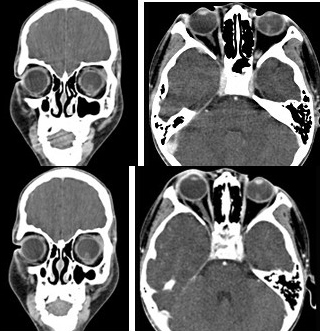

女性,46岁,自述左眼视物不清约三个月,CT扫描如图所示,请选择正确的描述或答案( )

A:双侧眼球未见病变

B:左侧玻璃体内偏后方见絮状高密度影

C:双侧眼环形态密度正常

D:考虑视网膜脱离

E:考虑玻璃体内出血